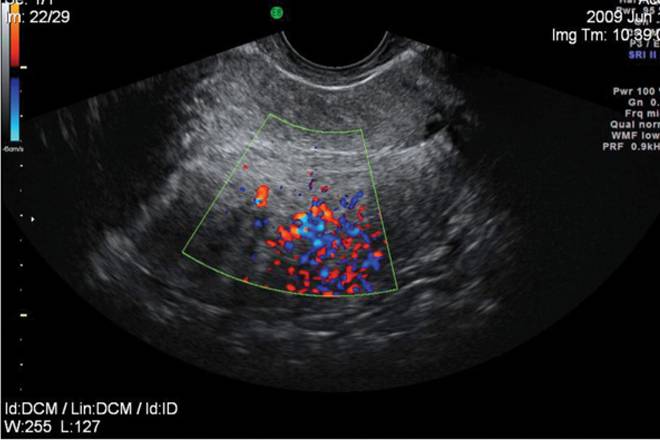

Исследование с ЦДК

Цветное доплеровское картирование (ЦДК) предоставляет возможность четко различать кисты и опухоли различных типов, что делает его популярным среди врачей как один из самых информативных методов диагностики. Киста не содержит кровеносных сосудов и представляет собой полую структуру, заполненную жидкостью. Применение ЦДК помогает специалисту определить состав новообразования и провести детальный анализ патологического очага.

Такой подход особенно важен перед проведением хирургического вмешательства, так как он позволяет уточнить расположение и структуру сосудов в пораженной ткани. Методика дает возможность оценить состояние сосудов, а также направление и скорость кровотока в области патологии. Информативность данного исследования позволяет заранее установить характер новообразования.